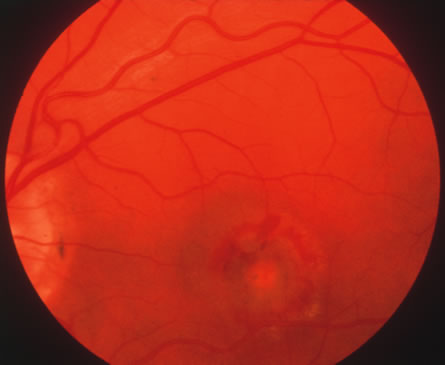

CMV retinitis is common in patients with AIDS. Perivascular granular white or yellowish infiltrates with hemorrhage are typical (Fig. 7). Minimal vitritis or anterior uveitis may be present. The posterior pole, including optic nerve, or peripheral retina may be involved. Optic neuritis may be retrobulbar. Resolution of retinal lesions reveals local retinal atrophy and pigment dispersion. Iridocyclitis may occur secondary to infection of ciliary processes. CMV retinitis in patients with AIDS is considered a poor prognostic sign in terms of life expectancy. Congenital CMV infection may also cause retinitis, as well as anterior uveitis, cataract, and optic atrophy. New foci of retinochoroiditis can develop in later years of congenital infection, and such infants require periodic reexamination as long as virus is shed in the urine.

Fig. 7. Cytomegalovirus retinitis in a patient with aquired immune deficiency syndrome (AIDS). Note the large area of retinal necrosis along with the perivascular distribution of the lesions.